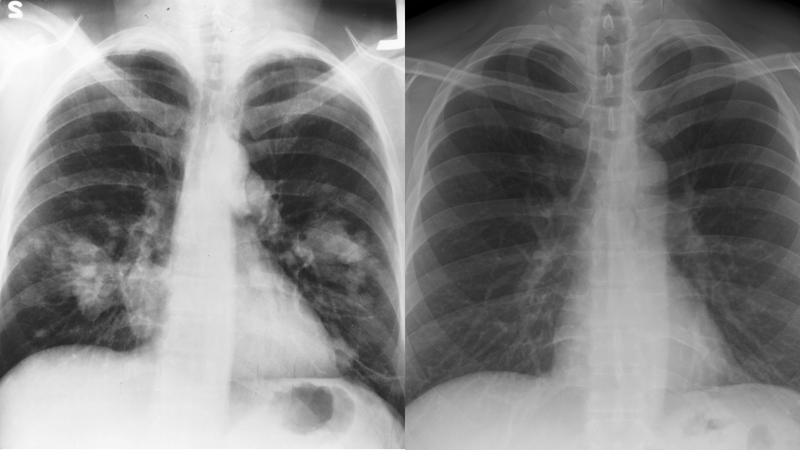

Trong y khoa, phổi trắng là hình ảnh mảng trắng bất thường trên X-quang hoặc CT scan, phản ánh những tổn thương đáng kể ở nhu mô phổi. Đây không phải bệnh lý riêng mà là dấu hiệu cảnh báo nhiều vấn đề hô hấp nguy hiểm như viêm phổi, lao hay ung thư phổi.

Phổi trắng là thuật ngữ mô tả hình ảnh bất thường ở phổi khi chụp X-quang hoặc CT ngực. Thông thường, phổi khỏe mạnh chứa nhiều khí nên hiện lên khá trong suốt, cho phép tia X đi qua dễ dàng. Tuy nhiên, khi nhu mô phổi bị viêm, chứa dịch, xơ hóa hoặc xuất hiện khối u, mật độ mô tăng lên khiến hình ảnh thu được trở thành vùng trắng mờ.

Điều đáng lưu ý là phổi trắng không phải một bệnh độc lập mà chỉ là biểu hiện hình ảnh. Bác sĩ cần kết hợp cùng triệu chứng lâm sàng và các xét nghiệm để xác định nguyên nhân thực sự. Tình trạng này có thể bắt nguồn từ nhiều nguyên nhân khác nhau.